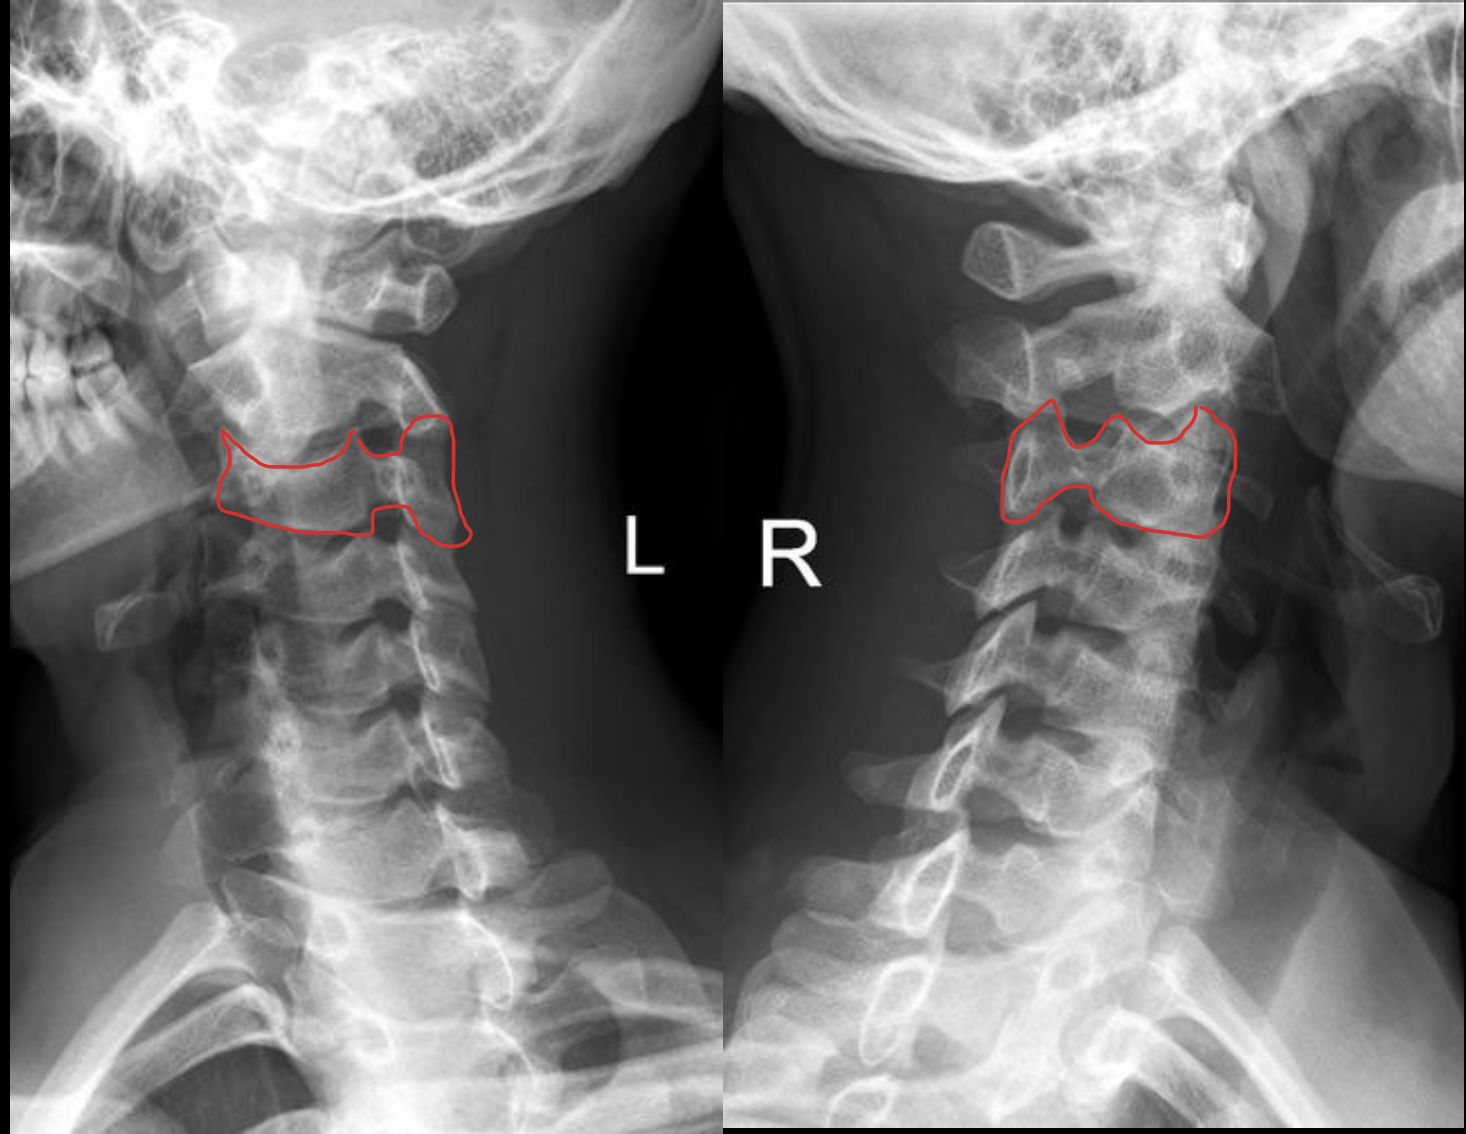

C3